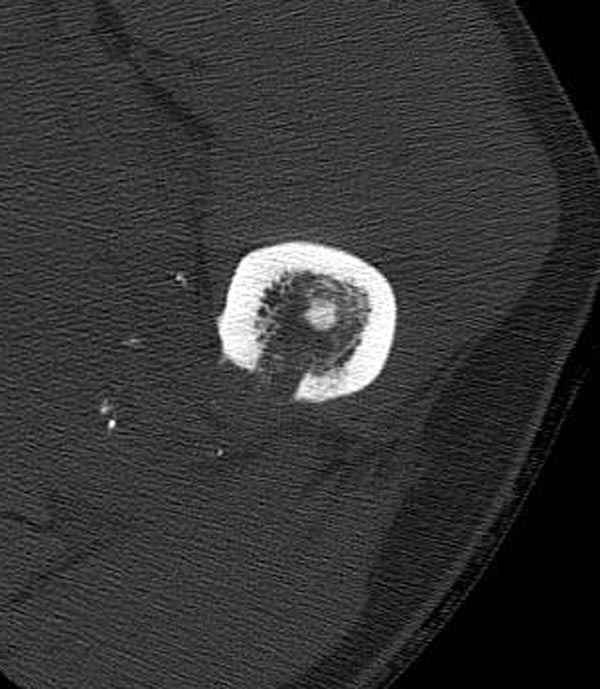

Методика штифтования при отсутствии большой зоны перелома как при онкологических профилактических штифтованиях, расверливание интрамедуллярного канала проводим с предварительным наложением дополнительного дренажного отверстия в дистальном отделе бедра (в данном случаи в канале оставили 6.5 мм канюлированный шуруп), иначе при создании давления в канале во время сверления имеется опасность эмболизации легочной артерии тромбом.